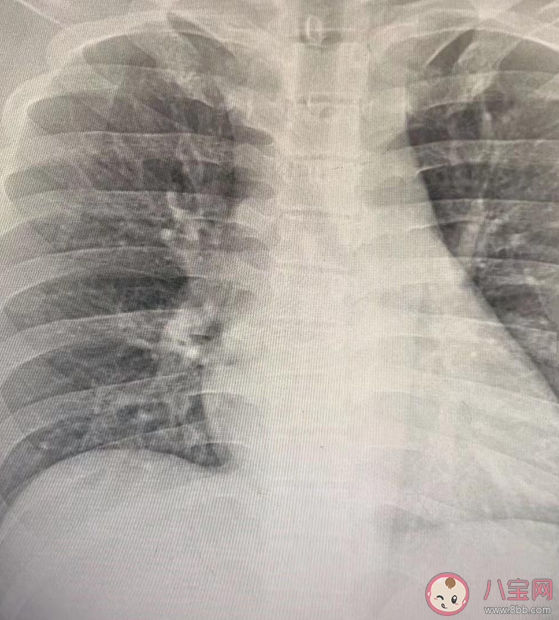

近日,男子在宠物医院用宠物医疗设备拍片检查引关注,1月1日,杭州一名男子在宠物医院用宠物医疗设备拍片检查引关注。2日,该宠物医院的负责人何先生回应称,男子系医院员工,因该店内员工出现新冠阳性后不断咳嗽,又没有时间去医院排队拍片检查,于是用店内设备检查是否出现“白肺”。

何先生称,拍摄的设备日常用于宠物骨头、肺部等器官检查,给人拍片也可1分钟成像,但没CT清楚不能作为诊断依据。目前店内员工身体已经恢复,已正常工作,不建议这样对人检查。

人在宠物医院拍片只能起到临时应急的作用,大致看看有没有出现白肺的情况,由于无法进行精确的诊断,所以不建议人来宠物医院检查。

因此用给动物做拍片的机械设备,给人进行拍片,拍出来的片子可能不准确,是不能作为诊疗判断的依据的。更有可能存在有重大的缺陷,有可能会怠误病情,造成误诊误断。

该拍片没有一点参考价值,宠物医院的医生无权对于人体的胸片作出诊断,医生也不会对宠物医院的胸片作出诊断。